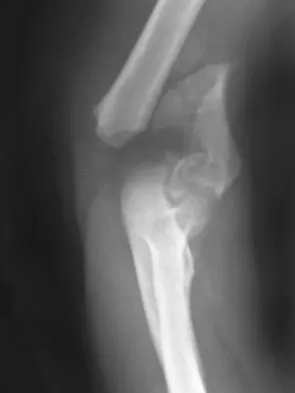

Figures 4a through 4c show the radiographs of a 43-year-old woman who sustained a twisting injury to her right ankle. She has ankle pain and tenderness medially and laterally. To help determine the optimal treatment, an external rotation stress radiograph of the ankle is obtained. This test is designed to evaluate the integrity of what structure?

Explanation

In the presence of a supination external rotation-type fracture of the distal fibula (Weber type B), stability of the ankle is best assessed by performing an external rotation stress AP view of the ankle. This test is used to assess the integrity of the deltoid ligament. The presence of a deltoid ligament rupture results in instability and generally is best managed surgically. The gravity stress test can also be used. Egol KA, Amirtharajah M, Tejwani NC, et al: Ankle stress test for predicting the need for surgical fixation of isolated fibular fractures. J Bone Joint Surg Am 2004;86:2393-2398. McConnell T, Creevy W, Tornetta P III: Stress examination of supination external rotation-type fibular fractures. J Bone Joint Surg Am 2004;86:2171-2178.